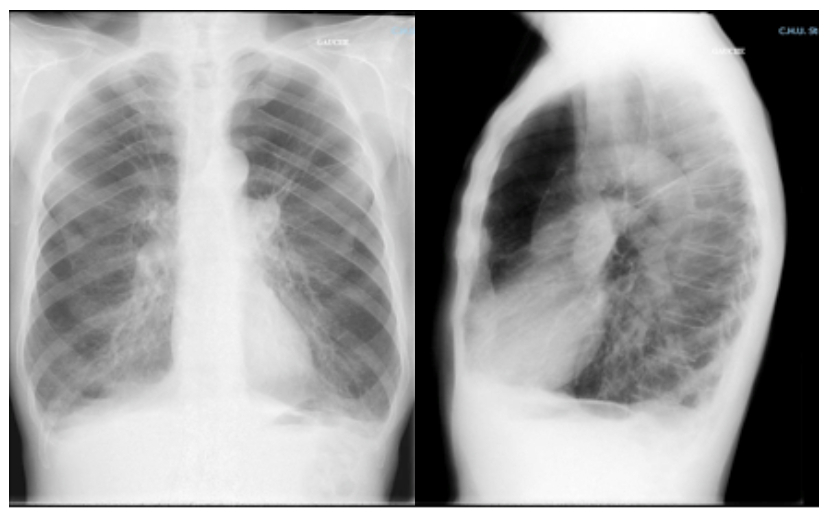

La radiographie de thorax est la suivante.

Figure 1.

Tableau radiologique pulmonaire typique d’une bronchopneumopathie chronique obstructive (BPCO) avec distension thoracique et emphysème. Le piège dans lequel il ne faut pas tomber est de penser à un syndrome interstitiel devant la présence de « traits » diffus faisant croire à des réticulations. Ces traits correspondent en fait aux structures bronchiques et vasculaires, toutes en direction du hile à la différence des réticulations du syndrome interstitiel qui seraient alors orientées dans toutes les directions, dessinant ainsi des polygones correspondant aux lobules pulmonaires. Ces structures bronchovasculaires paraissent très visibles par contraste (raréfaction de la trame microvasculaire environnante liée l’emphysème) et par la présence très probable d’une hypertension pulmonaire (dilatation des artères pulmonaires et de leurs branches).